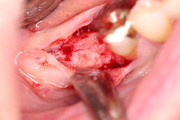

Socket + Implantation 3,5 Jahre Follow up

Nach Entfernung der Zähne 46 und 47, Augmentation DentOss fein, Adaptationsnähte, 6 Tage danach, Implantation nach 5 Monaten und ZE 45, 46 mit Zirkonkronen.Röntgenkontrolle nach einem Jahr und klinische Situation. 3,5 Jahre nach Socket.